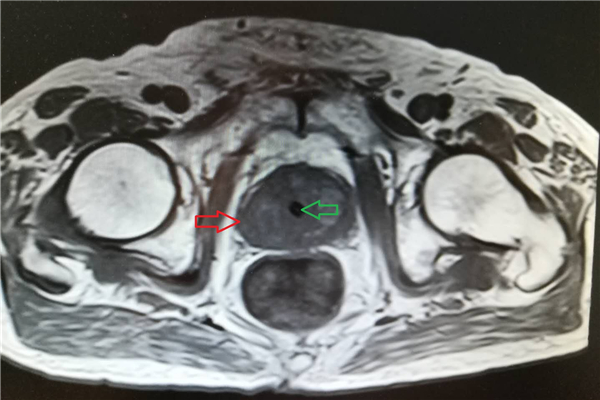

经过术前核磁,可明显看到增大的前列腺(如下图红色箭头所指,黄色箭头所指为膀胱,绿色箭头所指为尿道)